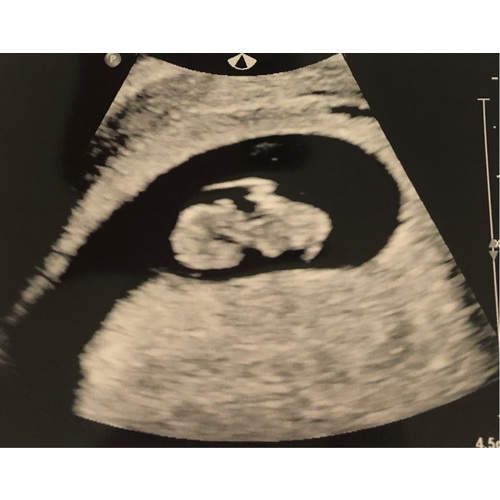

Echo gehad! Klein mini mensje met een kloppend hartje! 💝 over 3 weken weer een echo, spannend 🤞🏻